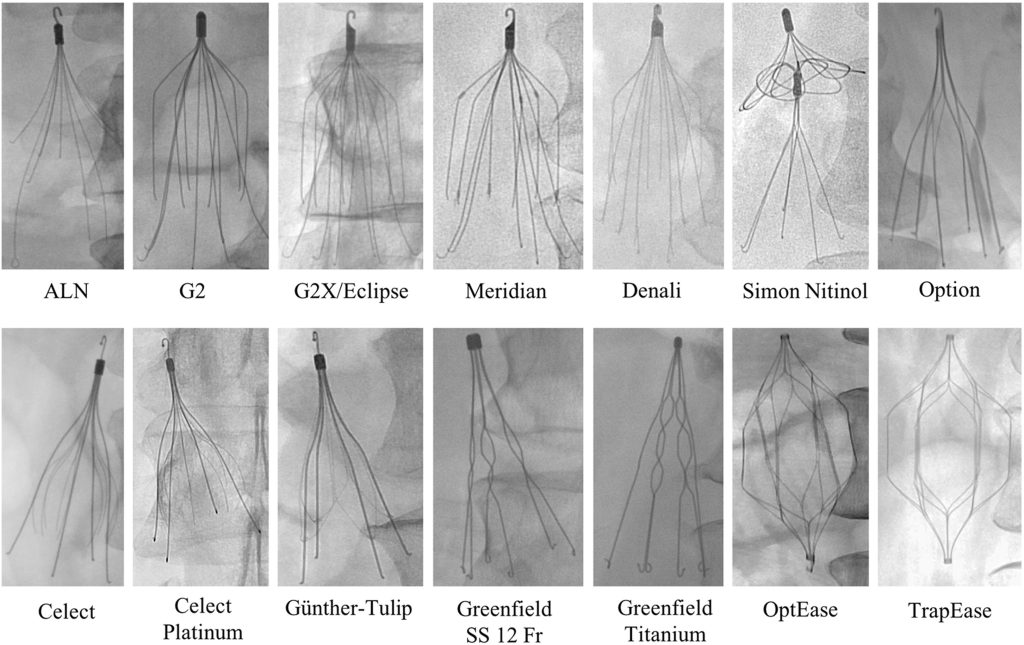

مدلهای دائمی:

- Greenfield (Boston Scientific): مدل کلاسیک stainless steel یا titanium، معرفیشده در 1973، با پاتنسی بالا و مناسب برای IVC تا 28 mm.

- TrapEase (Cordis/Johnson & Johnson): شکل cage-like، دائمی.

مدلهای قابل بازیابی (retrievable): - Denali (BD/Bard): پیشرفته، با نرخ بازیابی بالا و کاهش tilt/migration.

- Günther Tulip و Celect/Celect Platinum (Cook Medical): محبوب، با anchoring legs، اما ریسک perforation.

- Option (Argon Medical): مشابه Denali، اما گاهی سختتر بازیابی.

- OPTEASE (Cordis): retrievable تا مدت محدود، cage-like.

مدلهای قدیمیتر Bard (با عوارض بیشتر، منجر به lawsuits): - Recovery, G2, G2 Express, Eclipse, Meridian.

مدلهای نوین: - Sentry (Boston Scientific): bioconvertible، خودکار بازشونده.

- VenaTech Convertible (Braun).

انتخاب مدل بر اساس قطر IVC، مدت نیاز و ریسک عوارض است. تا 2025، تمرکز بر مدلهای با نرخ بازیابی بالا مانند Denali و Celect Platinum است.